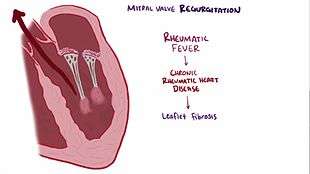

There are some valvular heart diseases that affect the mitral valve. Mitral stenosis is a narrowing of the valve. This can be heard as an opening snap in a heart sound which is not normally present.

Classic mitral valve prolapse is caused by an excess of connective tissue that thickens the spongiosa layer of the cusp and separates collagen bundles in the fibrosa. This weakens the cusps and adjacent tissue, resulting in an increased cuspal area and lengthening of the chordae tendineae. Elongation of the chordae tendineae often causes rupture, commonly to the chordae attached to the posterior cusp. Advanced lesions—also commonly involving the posterior leaflet—lead to leaflet folding, inversion, and displacement toward the left atrium.[4]

A valve prolapse can result in mitral insufficiency which is a regurgitation or backflow of blood due to the incomplete closure of the valve. Surgery can be performed to replace or repair a damaged valve. A less invasive method is that of mitral valvuloplasty which uses a balloon catheter to open up a stenotic valve.